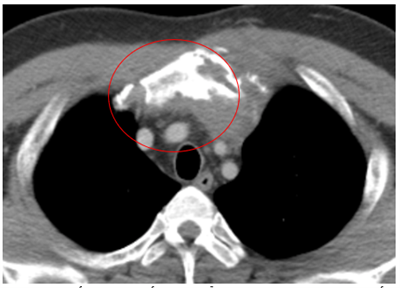

Ca lâm sàng: Điều trị đích bệnh nhân ung thư phổi không tế bào nhỏ giai đoạn muộn di căn nhiều cơ quan, tại Trung tâm Y học hạt nhân và Ung bướu – Bệnh viện Bạch Mai

Ung thư phổi là nguyên nhân hàng đầu gây tử vong do ung thư trên toàn thế giới. Trong đó, ung thư phổi không tế bào nhỏ (NSCLC) là thể thường gặp nhất, chiếm khoảng 85% các trường hợp [1]. Phần lớn bệnh nhân được chẩn đoán ở giai đoạn tiến...